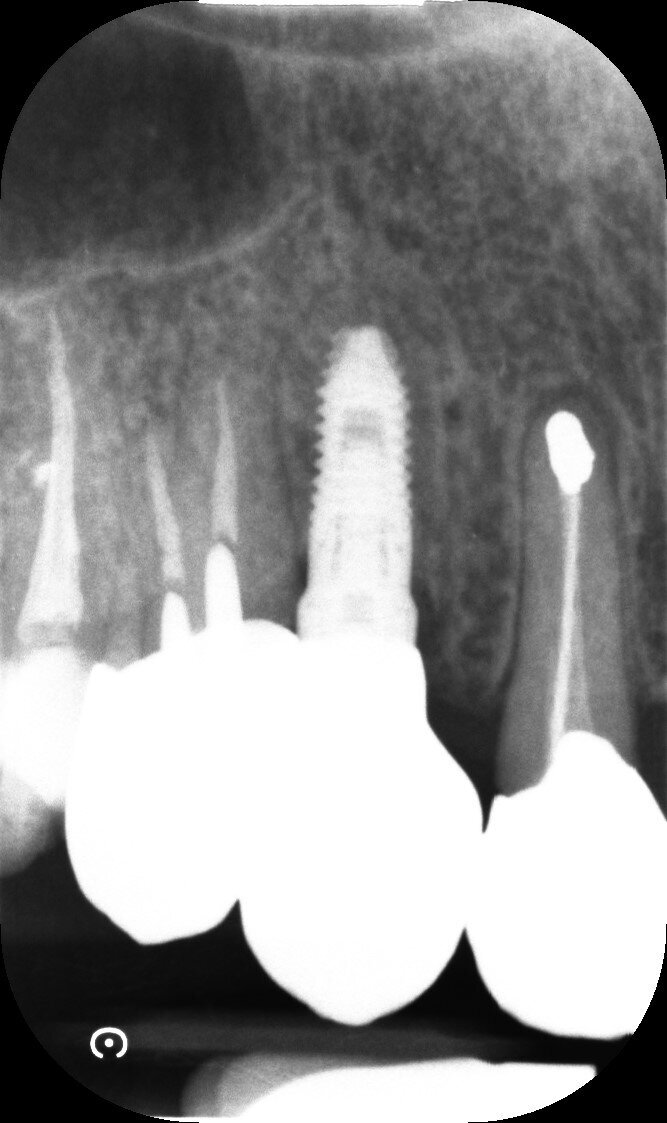

Il dente all’osservazione clinica e radiografica appare devitalizzato e ricostruito per mezzo di una perno moncone fuso e una corona in metallo ceramica collegata ad una corona sul dente 1.4 (Figg. 1, 2). All’esame parodontale si rileva un sondaggio puntiforme in zona palatale che indica la presenza di una frattura radicolare (Fig. 3). La paziente riporta una precedente apicectomia a carico del dente 1.2, come si evince dall’esame come-beam che ne evidenzia gli esiti a carico dell’osso apicale all’elemento 13 (Fig. 4).

Le corone sui denti 1.3 e 1.4 furono rimosse, il dente 1.3 fu estratto e l’alveolo fu riempito con una membrana di PRGF ottenuta tramite centrifugazione del sangue della paziente con il sistema Endoret e un provvisorio fu consegnato sui denti 1.3 e 1.4 (Fig. 5, 6). Dopo otto settimane fu eseguita una nuova cone-beam e la chirurgia fu pianificata (Fig. 7). Si eseguì un lembo a tutto spessore, fu eseguita l’osteotomia e fu inserito un impianto BTI Core 3.5 × 8.5. Un pilastro Unit fu avvitato e un tappo di guarigione fu applicato. L’osso ottenuto dalla fresatura mescolato con una membrana di PRGF fu applicato sul lato palatale per compensare una piccola deiscenza, una seconda membrana fu applicata sopra l’osso circostante e un innesto di tessuto connettivo prelevato dalla tuberosità fu suturato vestibolarmente per ricreare la bozza canina. Punti di sutura staccati furono eseguiti con un filo in PTFE (Figg. 8-11). Dopo quattro mesi il provvisorio fu rimosso e i tessuti apparivano sani e con un buon spessore di tessuto connettivo vestibolare per garantire la stabilità nel tempo del risultato. Fu eseguita un’impronta con la tecnica del cucchiaio aperto e dopo due settimane furono consegnate una corona in zirconio cementata sul dente 14 ed una avvitata sul denta 1.3. Il profilo di emergenza della corona sull’impianto appariva ideale. Purtroppo, a causa della mancanza del picco osseo sul versante distale del dente 1.2, non si ottenne una papilla di altezza adeguata. Ciononostante la paziente si disse soddisfatta del risultato e rifiutò ulteriori terapie per correggere il difetto residuo (Figg. 12-15).